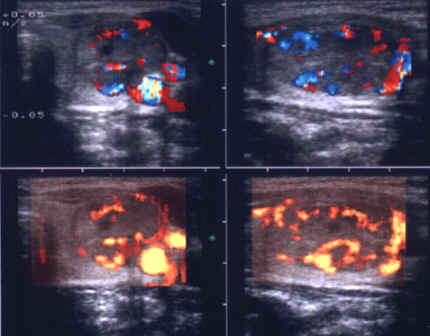

ecocolordoppler si powerdoppler- acelasi nodul

Vascularizatie interna, mai evidenta in powerdoppler.

Femeie 25 ani. Nodul unic in lobul stang, contur net, hipoecogen, respecta parenchimul din jur, neomogen, de 18x23x36 mm (7,5 cc).

Citoaspiratia cu ac subtire: nodul adenomatos.

Examen histologic postoperator: adenom trabecular fetal.

Acelasi caz. La doppler color - vascularizatie interna, mai evidenta in powerdoppler.